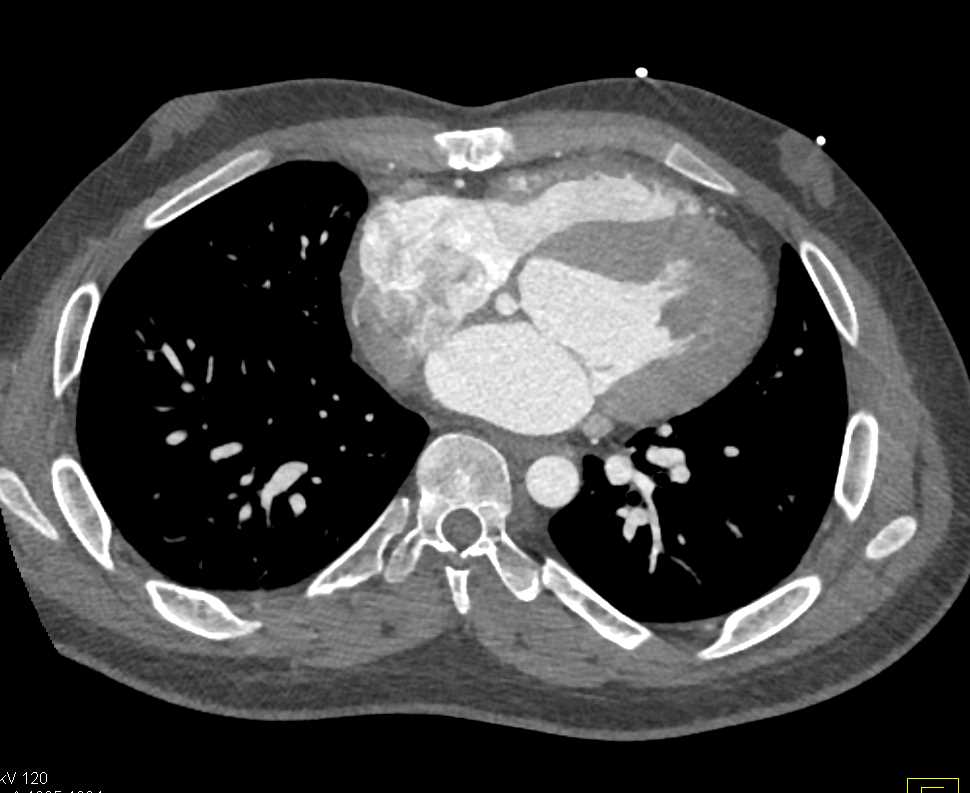

Aortic Valve Repair